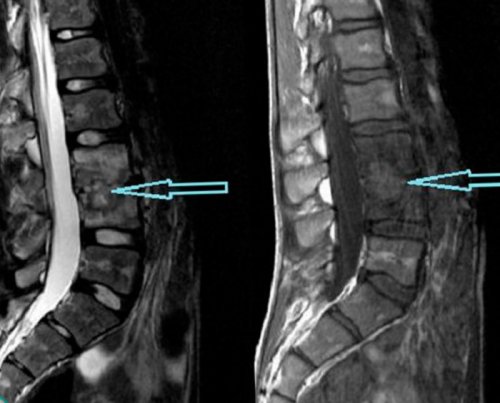

В зависимости от источника болей пациентам может рекомендоваться пару дней придерживаться постельного режима или наоборот увеличить уровень физической активности, но в разумных пределах. Например, боли, обусловленные компрессией нервов, требуют дать спине отдых на несколько дней. При других заболеваниях наоборот умеренная физическая нагрузка является одной из обязательных составляющих терапии. Она способствует повышению эффективности медикаментозного лечения, снижению риска развития осложнений и предотвращения инвалидизации.• отказаться от подъема тяжелых предметов и изнурительных занятий спортом;• МРТ – дает исчерпывающую информацию о состоянии мягких тканей и хрящей, в том числе межпозвоночных дисков, с помощью МРТ можно диагностировать межпозвонковые грыжи любых размеров, изменения в кровеносных сосудах, опухоли.Для подтверждения имеющихся предположений, точного выяснения причин появления болей проводится комплексное обследование пациента, которое может включать:Физиологические причины появления болей в поясницеБолезнь Бехтерева или анкилозирующий спондилоартрит – хроническое заболевание суставов, при котором в первую очередь поражается крестцово-подвздошное сочленение, суставы позвоночника и окружающие его мягкие ткани. При этом заболевании людей беспокоят боли в пояснице и крестце и скованность движений, но симптомы обычно бесследно исчезают во второй половине дня и ночью.Нередко больные обращаются за медицинской помощью спустя несколько лет после появления первых симптомов. В результате такого длительного течения воспалительного процесса в позвоночнике могут происходить необратимые изменения, которые в конечном итоге могут привести к обездвиженности и инвалидности.Остеохондроз является платой человечества за возможность прямо хождения. Для него характерно постепенное разрушение межпозвоночных дисков, их истончение, снижение эластичности и упругости. В результате чего они перестают справляться с нагрузками и могут выпячиваться. Таким образом формируются межпозвонковые грыжи.

• КТ – современный метод лучевой диагностики, позволяющий предельно четко визуализировать все костные структуры и обнаружить малейшие отклонения от нормы;

Для улучшения состояния пациента и быстрого купирования болей назначаются:• повысить уровень физической активности, но избегать переутомления и выполнения тяжелой работы (ежедневные прогулки, утренняя зарядка, выполнение специального комплекса ЛФК, занятия плаванием);В большинстве случаев изначально пациентам предлагается консервативное лечение, основным компонентом которого является медикаментозное лечение. В более сложных случаях дополнительно рекомендуется проведение курса физиотерапевтических процедур, мануальная терапия и ЛФК.• рентген – показывает наличие изменение в костных структурах позвоночника, признаков переломов, дает информацию о плотности костной ткани и позволяет диагностировать основные заболевания позвоночника, а также остеопороз (обнаружение патологий позвоночника является поводом для более досконального исследования с помощью КТ или МРТ);